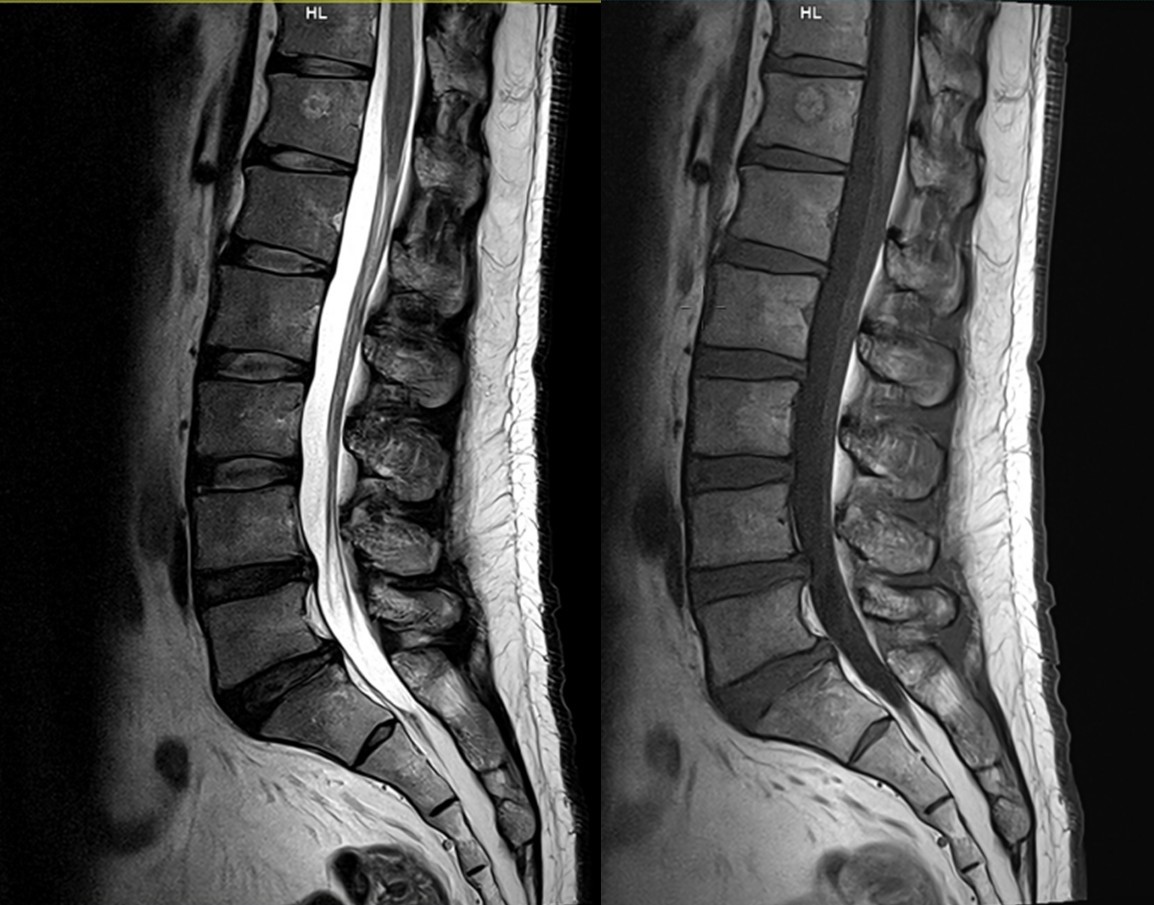

脊髄や椎間板などの組織を明瞭に描出することができます。椎間板ヘルニアによる脊椎神経の圧迫状態、脊椎圧迫骨折など脊椎疾患の診断に有用な検査です。

腰椎MRI画像

腰椎神経根画像